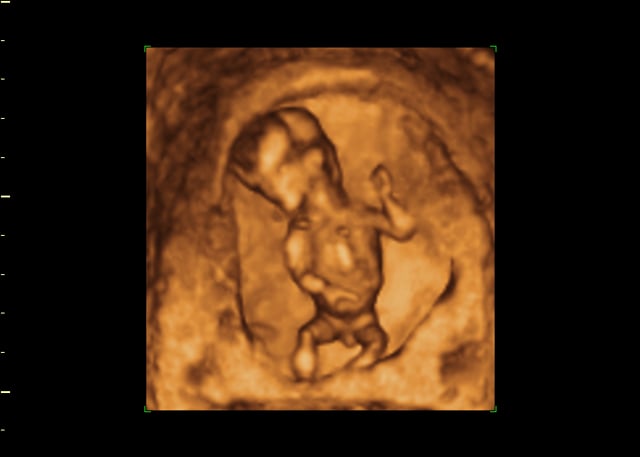

Explora los videos más recientes de los. 93103 mm de altura 50 g de peso. En esta semana 15 de embarazo el bebé está muy activo realiza un montón de movimientos traga líquido amniótico e incluso se puede llevar los dedos a la boca.

Cambios en el bebé en la semana 15 de embarazo. En la semana 15 de gestación el feto mide entre 9 y 10 centímetros y pesa unos 50 gramos el doble que la semana anterior.

15 Semanas De Gestacao Trocandofraldas Com Br